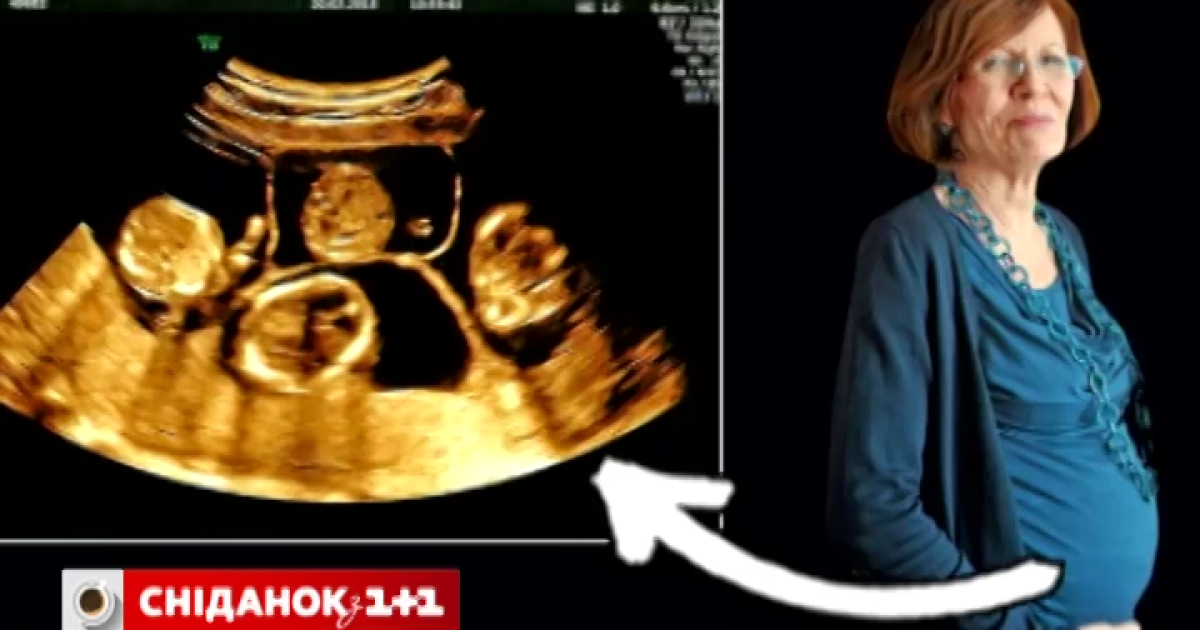

Аннегрет вже має 13 дітей і тепер чекає на четвірню

65-річна німкеня Аннегрет Раунінг має народити вже влітку. Цих пологів чекає вся Німеччина. Аннегрет вже має 13-х дітей. А під час штучного запліднення прижилися аж чотири ембріони. Іншими словами Аннегрет чекає на четвірню.

"Вона приїхала в Україну, отримала четверню. Виникають запитання про стан її психічного здоров'я. У 65 років народжувати ще 4 дитини, це треба визначити певні проблеми. Вірогідність того, що діти народяться здоровими -2-3 відсотки", - каже головний лікар клініки.